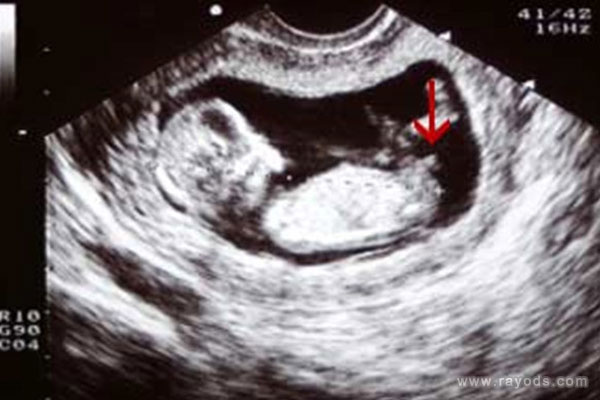

(男孩的nt图片)

13周nt图中男女特征是非常明显的,很多人都觉得这个时候孕周还小,胎儿还未正式开始发育。尽管如此,但在很多过来人看来,这个时候的nt图中男孩女孩已经有了区别了,胎儿身体姿势就已经给了暗示。

首先看nt图中胎儿整个身体的幅度,如果身子是弯着的,说明怀的是男孩,反之如果身子是平行的,则怀女孩,据说很多人都是根据这一点对比男女的不同的。

再者就看胎儿脊柱线和尾椎骨,按照男孩女孩发育的不同,男孩的脊柱线会大于30度甚至更多,身体明显有弯曲的弧度,而女孩的脊柱线一般都是小于30度的,看起来就是平缓的睡在妈妈肚子里。就对于这一点,老人们也有一个说法与之类似,那就是儿靠女睡,其意思就是儿子靠着妈妈,女儿则睡在妈妈肚子里。

最后就看胎儿的尾椎骨这里了,据说胎儿尾椎骨上翘的话则说明怀的是男孩,反之如果尾椎骨和身体保持平行的话则生女孩。尾椎骨是男女特征最大的区别点,因为这个地方是要发育生殖器的,尤其是男孩尾椎骨会上翘,这是在给生殖器发育留下空间,因此才会有这个姿势。

就根据以上说到的三个特征对比可以看出,男孩女孩之间的区别还是很大的,一个是nt图的姿势、一个是脊柱线大于小于角度,另一个就是尾椎骨上翘和平行,看起来好像的确很准确,但这是不是真的准呢?这一点就说不准了,其实这些所谓的方法都是已生宝妈们的所谓的经验总结,大家结合参考下就行了,不要太执念于结果。